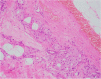

Apocrine change is recognised in benign, atypical and malignant lesions of the breast. Apocrine metaplasia, a frequent finding in the breast of women over the age of 25 years, is most commonly seen in benign cysts with a simple or papillary configuration. Apocrine change is also recognised in other benign lesions including sclerosing adenosis, now known as apocrine adenosis. Apocrine atypia usually refers to cytological atypia in which there is at least threefold variation in nuclear size but architectural atypia may also occur. The distinction between atypical apocrine hyperplasia and non-high-grade apocrine ductal carcinoma in situ may be difficult due to the relative rarity of these entities and the lack of validated diagnostic criteria. Lobular carcinoma in situ (LCIS) with apocrine change is considered to be a variant of pleomorphic LCIS. An apocrine variant of encapsulated papillary carcinoma is also recognised. Apocrine change is described in invasive carcinoma, including no special type, lobular, micropapillary and mucinous variants. The recent WHO 2019 update recognises 'carcinoma with apocrine differentiation' as a special type breast carcinoma based on the presence of apocrine morphology in at least 90% of the tumour. Tumours with apocrine morphology are usually but not always hormone receptor negative. Human epidermal growth factor receptor 2 (HER-2) status is variable. Molecular studies have identified breast tumours with apocrine features and high expression of androgen receptor mRNA including 'luminal androgen receptor tumours' and 'molecular apocrine tumours'. The term 'pure apocrine carcinoma' has been proposed to describe an invasive carcinoma with apocrine morphology that is oestrogen and progesterone receptor negative and androgen receptor positive. HER-2 status may be positive or negative. This article reviews the pathology of benign, atypical and malignant apocrine lesions of the breast, with emphasis on diagnostic criteria including an approach to evaluation of apocrine lesions on needle core biopsy, and recent advances in our understanding of invasive apocrine carcinoma.